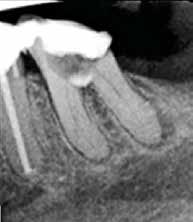

Fig. 1. A. Udsnit af panoramaoptagelse viser Ca(OH)2 uden for foramen apicale i en overkæbemolar og i sinus maxillaris (pil). B. Periapikal optagelse viser Ca(OH)2 uden for foramen apicale (pil) i en central incisiv. Tilfældet krævede kirurgisk indgreb.

Fig. 1 A. An orthopantomography section showing Ca(OH)2 beyond the apical foramen of maxillary first into the maxillary sinus (arrow) and (B) a periapical radiograph with Ca(OH)2 extrusion beyond the apical foramen (arrow) of a central incisor which required surgical intervention.

Ved mistanke om malpraksis vurderer man behandlerens handlinger i alle stadier i relation til opgavens kompleksitet og tager stilling til, om disse lever op til normen for almindelig anerkendt faglig standard. De mest omfattende skadevirkninger ses i forbindelse med anvendelse af endodontiske skyllevæsker og andre medikamenter, fx ulykker med natriumhypoklorit eller skader på nervevæv eller i sinus som følge af udpresning af calciumhydroxid igennem foramen apicale (Fig. 1A og B) (5,6). Sådanne uheld vurderes ofte til at være undgåelige, idet tandlægen ikke har levet op til normal faglig standard. Frygt for at begå procedurefejl eller andre utilsigtede hændelser bør dog ikke få klinikeren til helt at afstå fra at foretage endodontiske behandlinger (7).